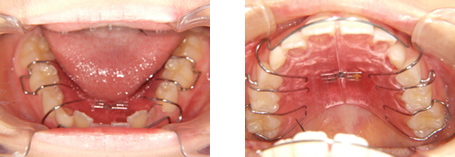

ワイヤー矯正治療(2021年1月~ 約1年)

ワイヤー矯正により歯をきれいに並べつつ上下で噛めるよう動かします。

【費用】上:110,000円/下:110,000円/ワイヤー交換(5本):55,000円(現在の費用は異なります)

【矯正期間】約1年